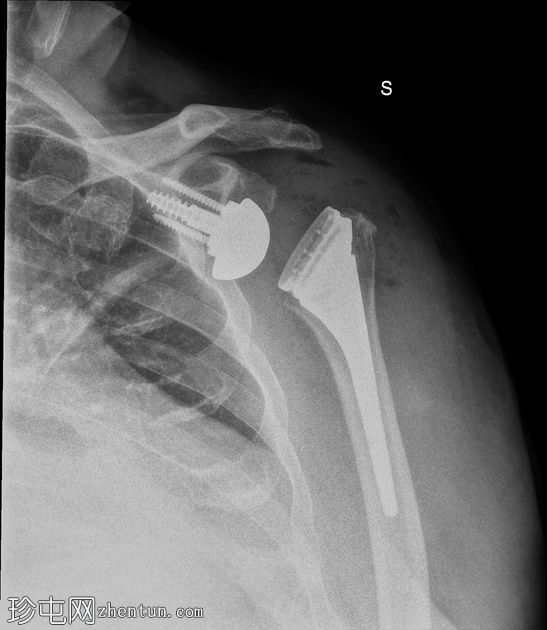

2.jpg

侧面

胸部侧面图:肱骨假体前脱位,盂球固定到位。和纵隔正常。无胸腔积液。